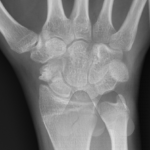

De Quervain’s tenosynovitis is a condition causing pain and swelling around the tendons that move the thumb. Patients often feel an ache or sharp pain near the base of the thumb or thumb side of the wrist when they are gripping or twisting. It can be caused by repetitive activities and commonly affects new mothers.